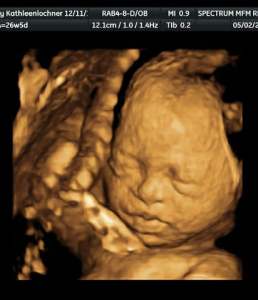

Ivy Ultrasound 3